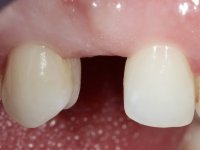

Female patient, 43 years old, non-smoker. Showed an edentulous space in the upper right canine area, resulting from tooth 1.3 impaction. The space had a mesio-distal diameter reduced to the normal size of the upper canine. This is consistent with the presence in the arch of the deciduous canine up to two years ago). Orthopantomography allows clearly view of tooth 1.3 impaction.The patient has a thick gingival phenotype and tolerable oral hygiene.

The proposed treatment results from the limitations imposed by the patient, who refused an orthodontical pull of the canine into the edntulous space, and was unwilling to extract the impacted canine and place an implant in the zone of 1.3. Thus, the confection of a Maryland Bridge was proposed, with a Zr infrastructure and two retainers. The mesial retainer would be bonded to the palatal face of the tooth 1.2 and the distal retainer was to be bonded to the palatal wall of tooth 1.4.